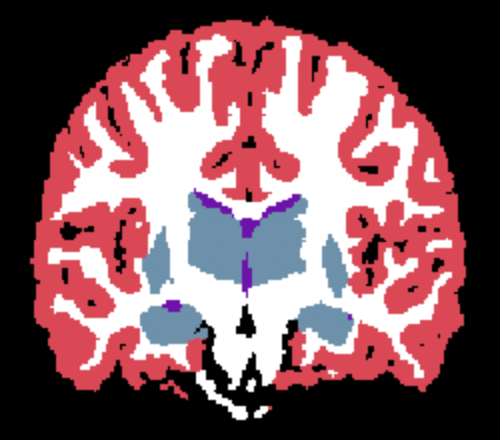

Results. Qualitative segmentation results are presented in Figure 3 and quantitative results are summarized in Table 5. Figure 3 shows that Learn2Synth produces cleaned and more accurate segmentation results compared to SAMSEG and naive SynthSeg, which is further validated by the higher Dice scores reported in Table 5. Learn2Synth also obtains higher Dice scores than the two SynthSeg variants that incorporate real data. These results highlight the effectiveness of Learn2Synth in enhancing segmentation quality for complex real-world data.

Here, we use both the INU model described in Equation 7 and the homogeneous noise model described in Equation 8. For the former, we use random fields with increasing spatial frequency (). We denote the corresponding learnable parameters , and , with preset values . Noise-free target “real”, and learned images are shown in Figure 2. Inference results for the value of the noise parameter are reported in Table 3, and are in line with those obtained in the noise-only experiment.

| (a) Noise-free image | (b) Learned image | (c) Real image |